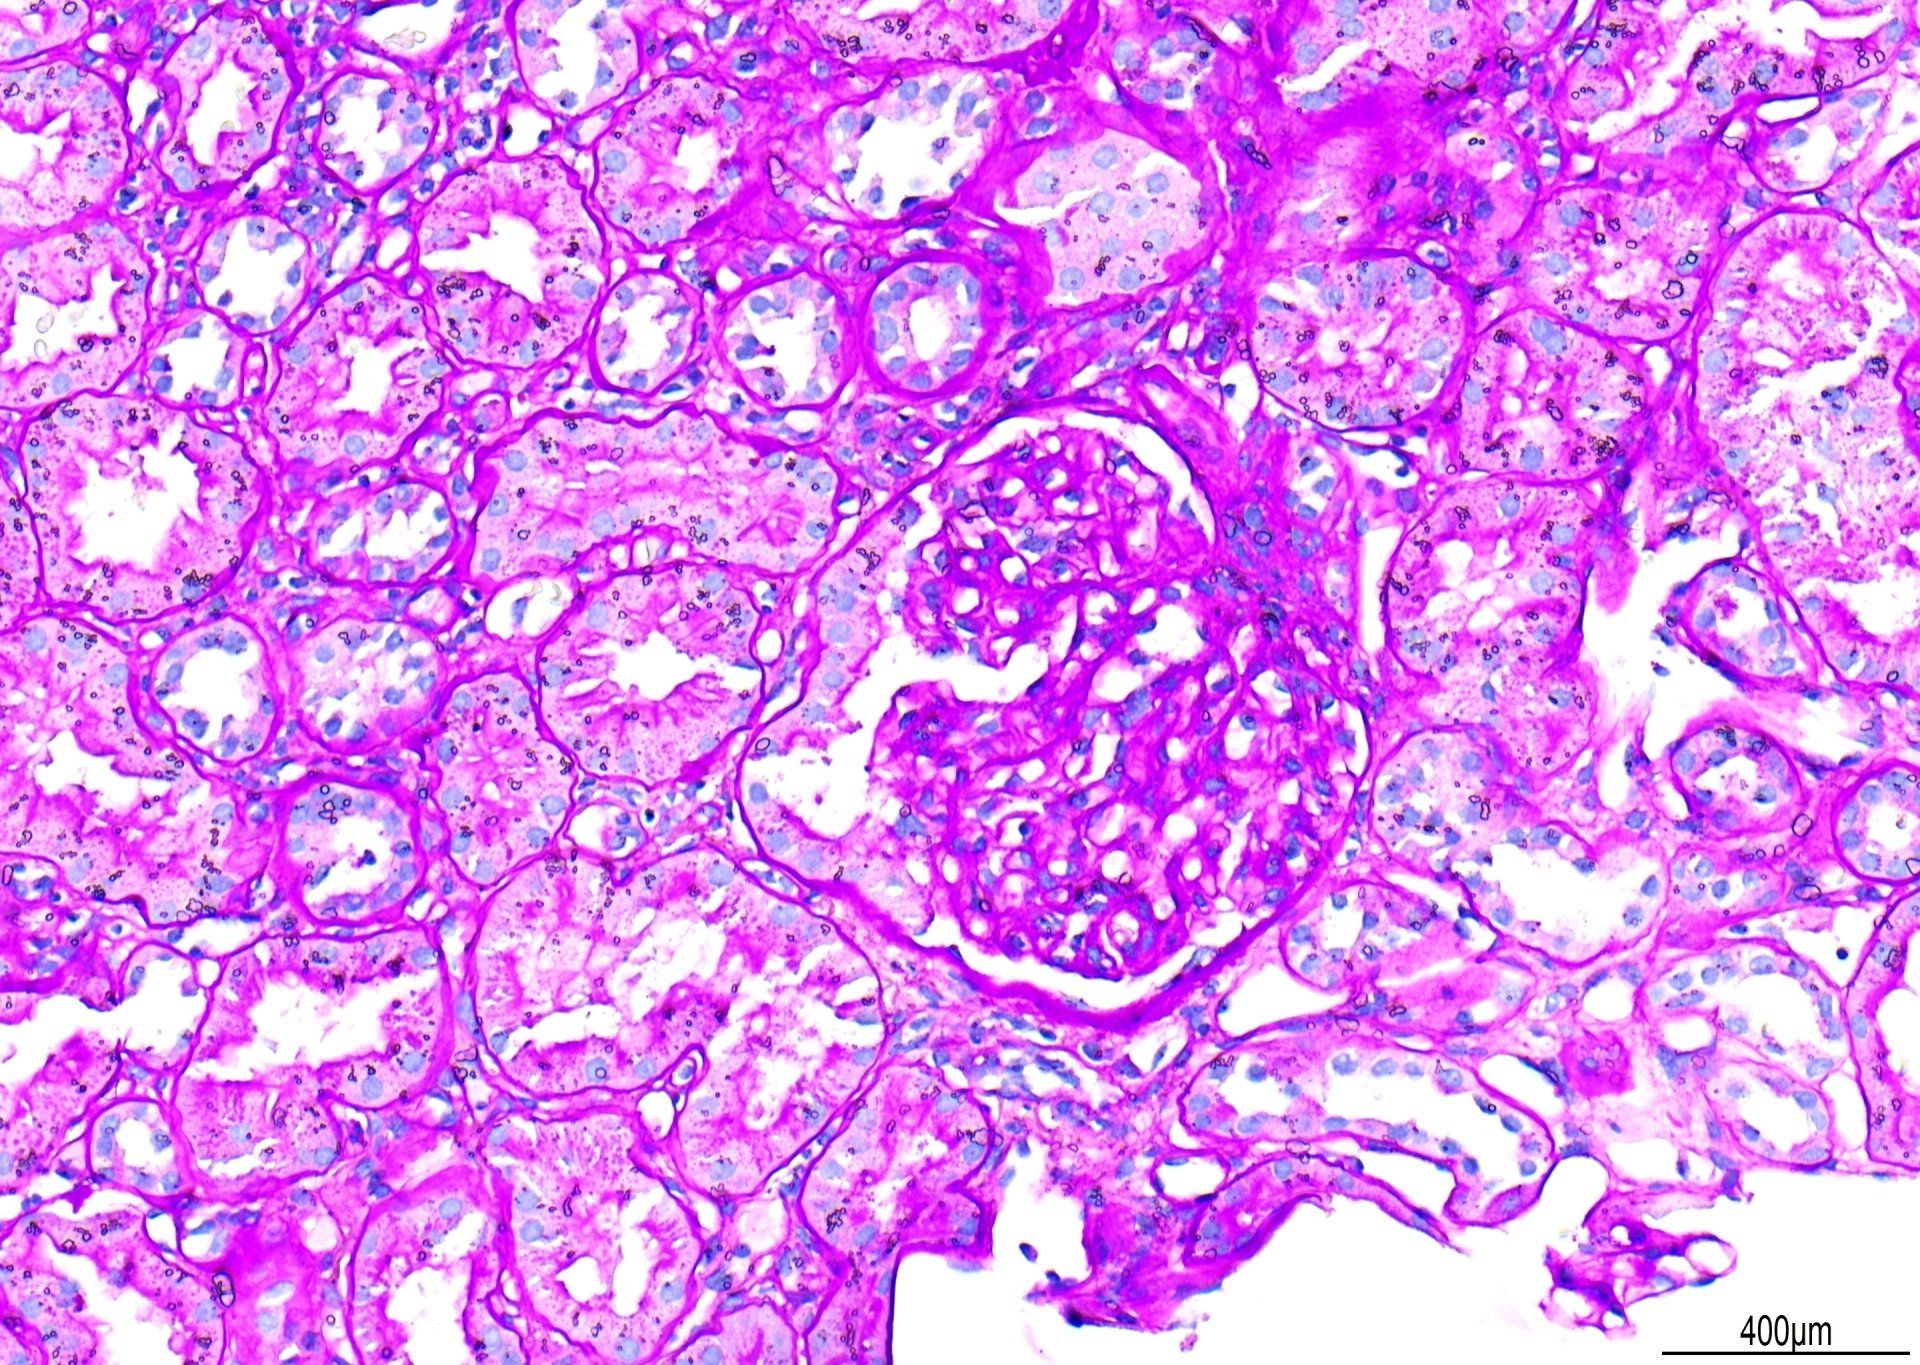

PAS - Schema renale

Questo è un esempio di colorazione PAS, osservato a 20x. Sono stati sottratti punti per la "colorazione di fondo primaria". Sebbene le membrane basali glomerulari siano ben colorate, il contrasto potrebbe essere migliore se ci fosse una minore colorazione di fondo di Schiff. Inoltre, sono state osservate goccioline d'acqua sotto il coprioggetto. Il punteggio complessivo per questa sezione è stato di 7/10.